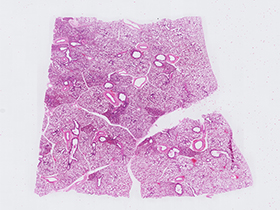

Parénquima pulmonar (tinción H&E)